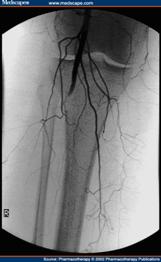

A. 動脈攝影:可查出血管阻塞之部位及阻塞之程度,於決定是否進行血管重建手術時,此為一必要之例行性檢查。

D. 血管腔內支架放置手術:以特殊的導管進入病人血管內,在精密的血管攝影輔助下,以各種導線或動脈血管擴張氣或置放血管內支架來打開嚴重狹窄或阻塞的血管。在精密的血管攝影輔助下,以各種導線或動脈 血管擴張氣或置放血管內支架來打開嚴重狹窄或阻塞的血管。 血管內支架手術的作法是在局部或是區域麻醉方式下,由病人的大腿經由一個小傷口,以特殊的導管進入病人血管內,在精密的血管攝影輔助下,以各種導線或動脈血管擴張氣球打通阻塞的血管,之後再置入適當尺寸及長度的血管內支架來維持血流的暢通,使得原本缺少動脈血流的遠端血管得到血流的再灌注,達成治療目的。由於血管阻塞複雜程度因人而異,血管腔內介入性手術不一定能夠解除所有的問題。 因醫師純熟的技術及醫療儀器科技化,已將併發症之發生減至最低。但有些病人仍有可能無法保住壞死的肢體。由於不用放置人工血管,所以手術範圍小,沒有傳統手術過後肢體腫脹的問題。因為所有的治療都在血管內完成,不用作血管的縫合,也大大地縮短了手術時間和術後諸如感染、出血等併發症的可能性。 一般傳統的血管繞道手術,在手術之後可能需要住院一個星期至兩個星期的時間才能出院,由於手術的時間長、範圍廣,再加上肢體需要一段時間來適應人工血管,所以患肢通常是在一、兩個月以後才完全復原。如果單純以血管內支架手術就得以治療的周邊動脈血管阻塞性疾病,通常在治療後就可以馬上下床活動,一至三天就得以出院,對於日常生活及活動影響極小。

其主要是利用高壓性的小氣球來打開阻塞的血管,或置放血管內支架來打開嚴重狹窄或阻塞的血管。 一般施行經皮血管內整形術只需局部麻醉並於手術室中進行,通常會將導管插入血管內,達正確位置後,注射顯影劑。 依血管病變程度醫師會決定是否執行氣球擴張術或裝置血管支架。整個手術治療約需1至3個小時,結束時即將全部導管拔除,傷口處直接加壓,直到確定沒有出血現象後,覆蓋無菌紗布,並以沙袋繼續加壓止血。